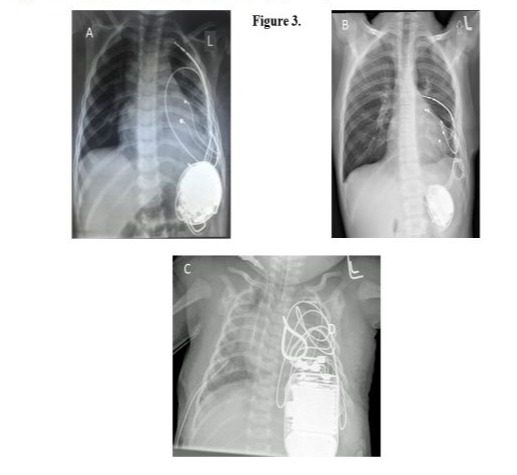

The implantation technique included a small anterolateral thoracotomy, usually via the 5th intercostal space with sub-pleural ICD lead placement in 22 children and sternotomy with pericardial ICD lead placement in 6 children (Figure 1A-D).

The operations were performed between 2004 and 2021 in our institution. Usually, the ICD lead was placed through the 4th intercostal space in a tunnel created under the parietal pleural wall (Figure 1B). We used ICD leads from St. Jude Medical in 22 patients and from Medtronic in the remaining 6 patients (Table 1).

In 3 of the 6 sternotomy patients, the ICD was implanted during cardiopulmonary bypass to repair heart defects, while the remaining 3 patients had an ICD implanted without a cardiopulmonary bypass. In 5 of the 6 sternotomy patients, the ICD lead was placed through the epicardial transverse sinus; an epicardial ICD patch was implanted in 1 patient (Figure 1D,E). All of our patients required pacing leads. We used dual-chamber pacing in 15 children and single-chamber pacing in the remaining 13 children (Figure 2).

To place the pacing lead, the pericardium was opened carefully and according to the anatomy of the phrenic nerve, parallel to its course. The apex and wall of the left ventricle were exposed, as was the appendage of the left atrium, where necessary. The pacing lead was fixed on the epicardial surface of the left ventricle according to the anatomy of the left coronary artery and its branches, especially in small children. If a patient required dual-chamber pacing, the atrial pacing lead was fixed to the surface of the left atrial appendage. We used pacing leads from Medtronic in all 28 patients (Table 1). Ethicon Prolene 6/0 and 5/0 monofilament sutures were used to affix the pacing wires. The ventricular and atrial leads were tested for sensing and pacing thresholds; the impedance of the pacing and ICD lead coil were measured. An ICD generator was placed in a pocket created through a subcostal incision under the left thoracic rib arch, below the diaphragm and above the peritoneum. The ends of the pacing wires, as well as the ICD lead, were translocated from the pleural cavity to the ICD pocket. When connected to ICD, the device was affixed and sutured to the left thoracic rib arch using nonabsorbable Ethicon Ethibond polyester sutures to avoid the device migrating (Figure 1C,D,E). At the end of the procedure, a test of the defibrillation thresholds was performed. We used ICDs from St. Jude Medical, Medtronic, and Biotronic (Table 1).

A chest tube sized according to the patient’s weight was placed in the left pleura and the wound was closed. The chest tube was usually removed on the next postoperative day. In the case of ICD lead implantation through the sternotomy, the ICD lead was placed in the transverse sinus with three fixation points to the surrounding tissues: in the area of the superior vena cava, in the pericardium at the pulmonary artery trunk, and in the pericardium at the apex of the heart. Pacing leads were implanted either on the right atrial surface and on the anterior surface of the right ventricle or on the left ventricular and left atrial surfaces. As with the sub-pleural technique, an ICD pocket was created under the left costal arch (Figure 1C,D,E).